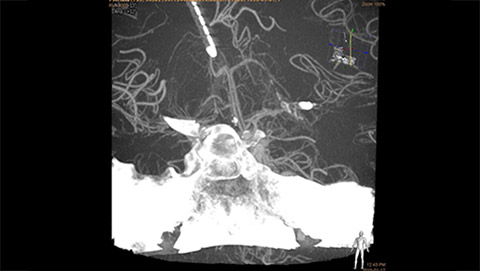

VasoCT (Allura X-ray system with dedicated EPX settings + XperCT + intravenous contrast injection) provides high-resolution imaging of intracranial arteries to help visualize location, size, and direction of an occlusion in case of Ischemic Stroke.

VasoCT visualizes small intra-cranial devices in vessel context with unmatched spatial resolution. Metal Artifact Reduction decreases streaking artifacts as from coil mass close to intra-cranial devices.

Stroke treatment is growing, fueled by availability of new devices. Philips Stroke Suite contains: XperCT, VasoCT, MR/CT Roadmap, XperGuide, FlexVision XL, and Roadmap Pro.